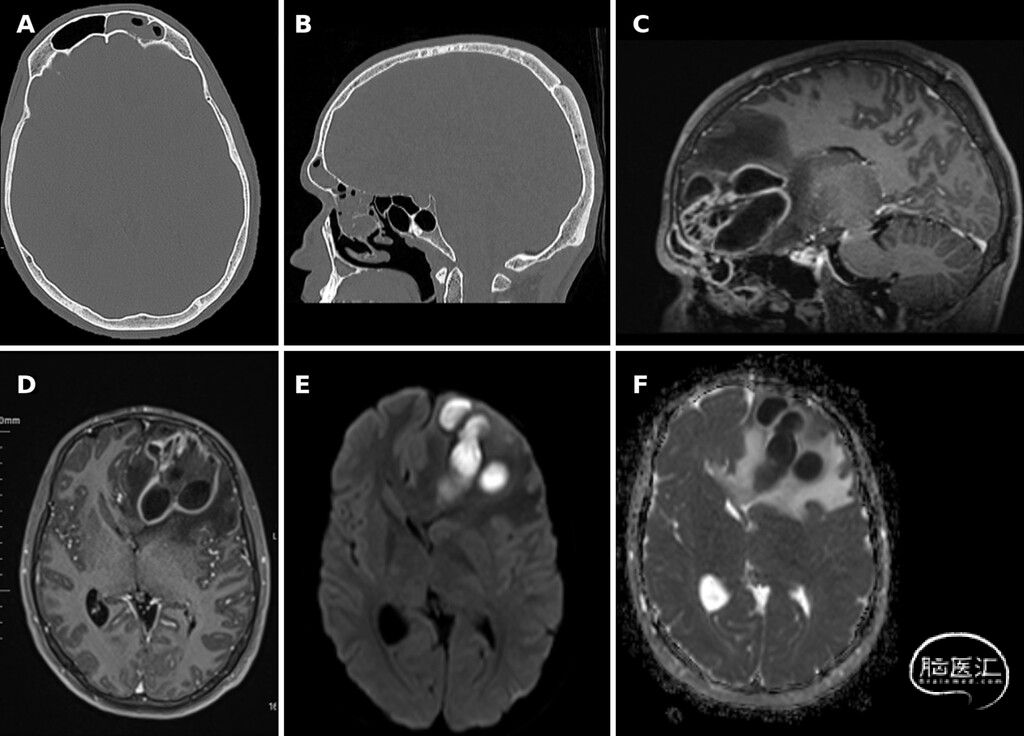

● 头颅平扫CT最初显示,左侧额叶多发低密度灶,病灶周围伴血管源性水肿。随后行头颅增强MRI进一步确诊与评估,结果显示,多房性环形强化脓肿,中央弥散受限,伴显著占位效应。鼻窦CT与MRI示,黏膜增厚、管腔内低密度影及局部骨质不规则,符合活动性鼻窦炎表现(图1)。

图1:A、B:鼻窦影像,提示感染的可疑来源。CT显示窦壁局部骨质缺损。C-F:术前脑部MRI,显示左侧额叶多房性脑脓肿。病灶在T1加权像呈低信号,T2加权像呈高信号,增强扫描可见厚壁环形强化的脓腔包膜,病灶周围伴明显血管源性水肿及占位效应。